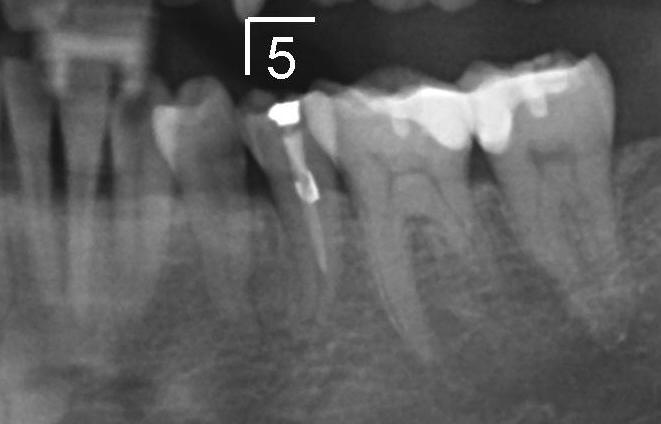

图三放大显示左下五根管弯曲,根管充填没有进入根尖,回